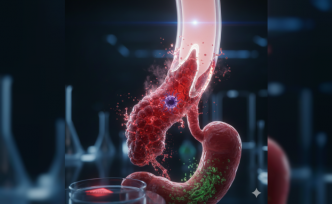

Bağışıklık Sistemi Kendi Kanına Karşı: Antifosfolipid Sendromu Tehlikesi

Vücudun savunma mekanizması bazen yönünü şaşırarak kendi sağlıklı hücrelerine saldırabiliyor. Tıp dünyasında Antifosfolipid Sendromu (APS) olarak bilinen bu durum, halk arasında daha çok "yapışkan kan" adıyla anılıyor. Kandaki proteinlere karşı gelişen hatalı antikorlar, damar tıkanıklıklarına ve hamilelik süreçlerinde ciddi risklere yol açmakta.